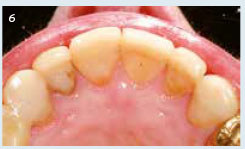

Afb. 6

Occlusaal aanzicht van het bovenfront. Zelfs de 12 kon worden opgebouwd met composiet en is gespalkt aan de 13.